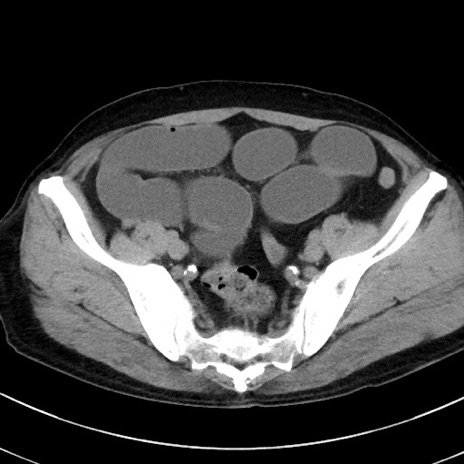

冠状断像

【症例】70歳代 男性

【主訴】腹痛・嘔吐

【現病歴】昨晩より、嘔吐・腹痛あり。今朝になっても嘔吐あり。来院。

【既往歴】心臓バイパス手術、開腹胆摘、腸閉塞

【身体所見】BP 107/71mmHg、HR 116/min、腹部:平坦、軟、下腹部に軽度圧痛あり。反跳痛なし。

【データ】WBC 15100、CRP 0.32